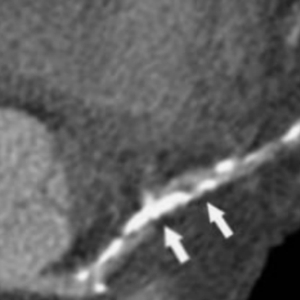

白色部分为钙化的“硬石头”

陈大爷冠脉造影后进一步完善了OCT检查结果提示:右冠脉中段开始弥漫性纤维钙化斑块形成,局部呈环形钙化,最小管腔面积仅2.6mm²,导丝无法到达血管远端,更换导丝后到达血管远端,但不能充分预扩张,应用传统的切割球囊处理后仍无法达到满意的预处理效果。心内科管浩副主任带领冠脉介入小组经过对患者冠脉情况的充分评估讨论,最终决定使用Shockwave冲击波球囊对患者进行治疗。